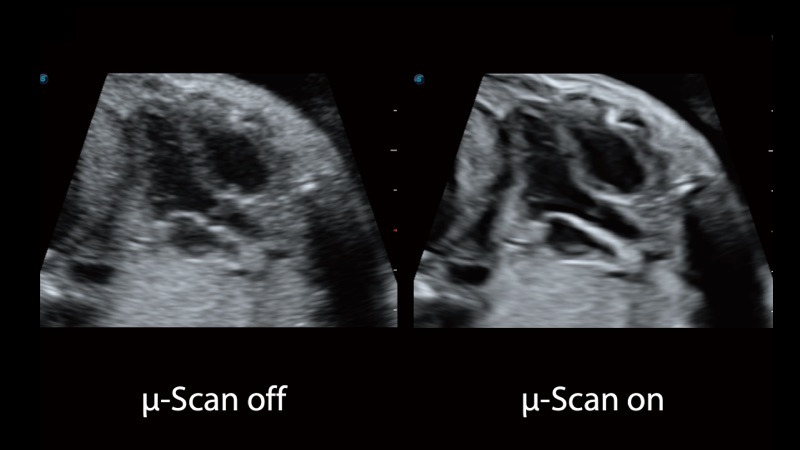

開(kāi)立醫(yī)療通過(guò)不斷的技術(shù)創(chuàng)新,為大眾的生命健康提供持續(xù)關(guān)愛(ài)。P12 Plus采用全新一代超聲成像平臺(tái),新平臺(tái)旨在將真實(shí)還原組織解剖結(jié)構(gòu)作為首要目標(biāo)。平臺(tái)采用全新集成化硬件模塊,搭載新一代芯片,系統(tǒng)性能得到大幅提升,為您的診斷提供了豐富的臨床信息。優(yōu)異的圖像表現(xiàn),豐富的探頭配置,全面的應(yīng)用功能,為您日常診斷提供了可靠的助手。